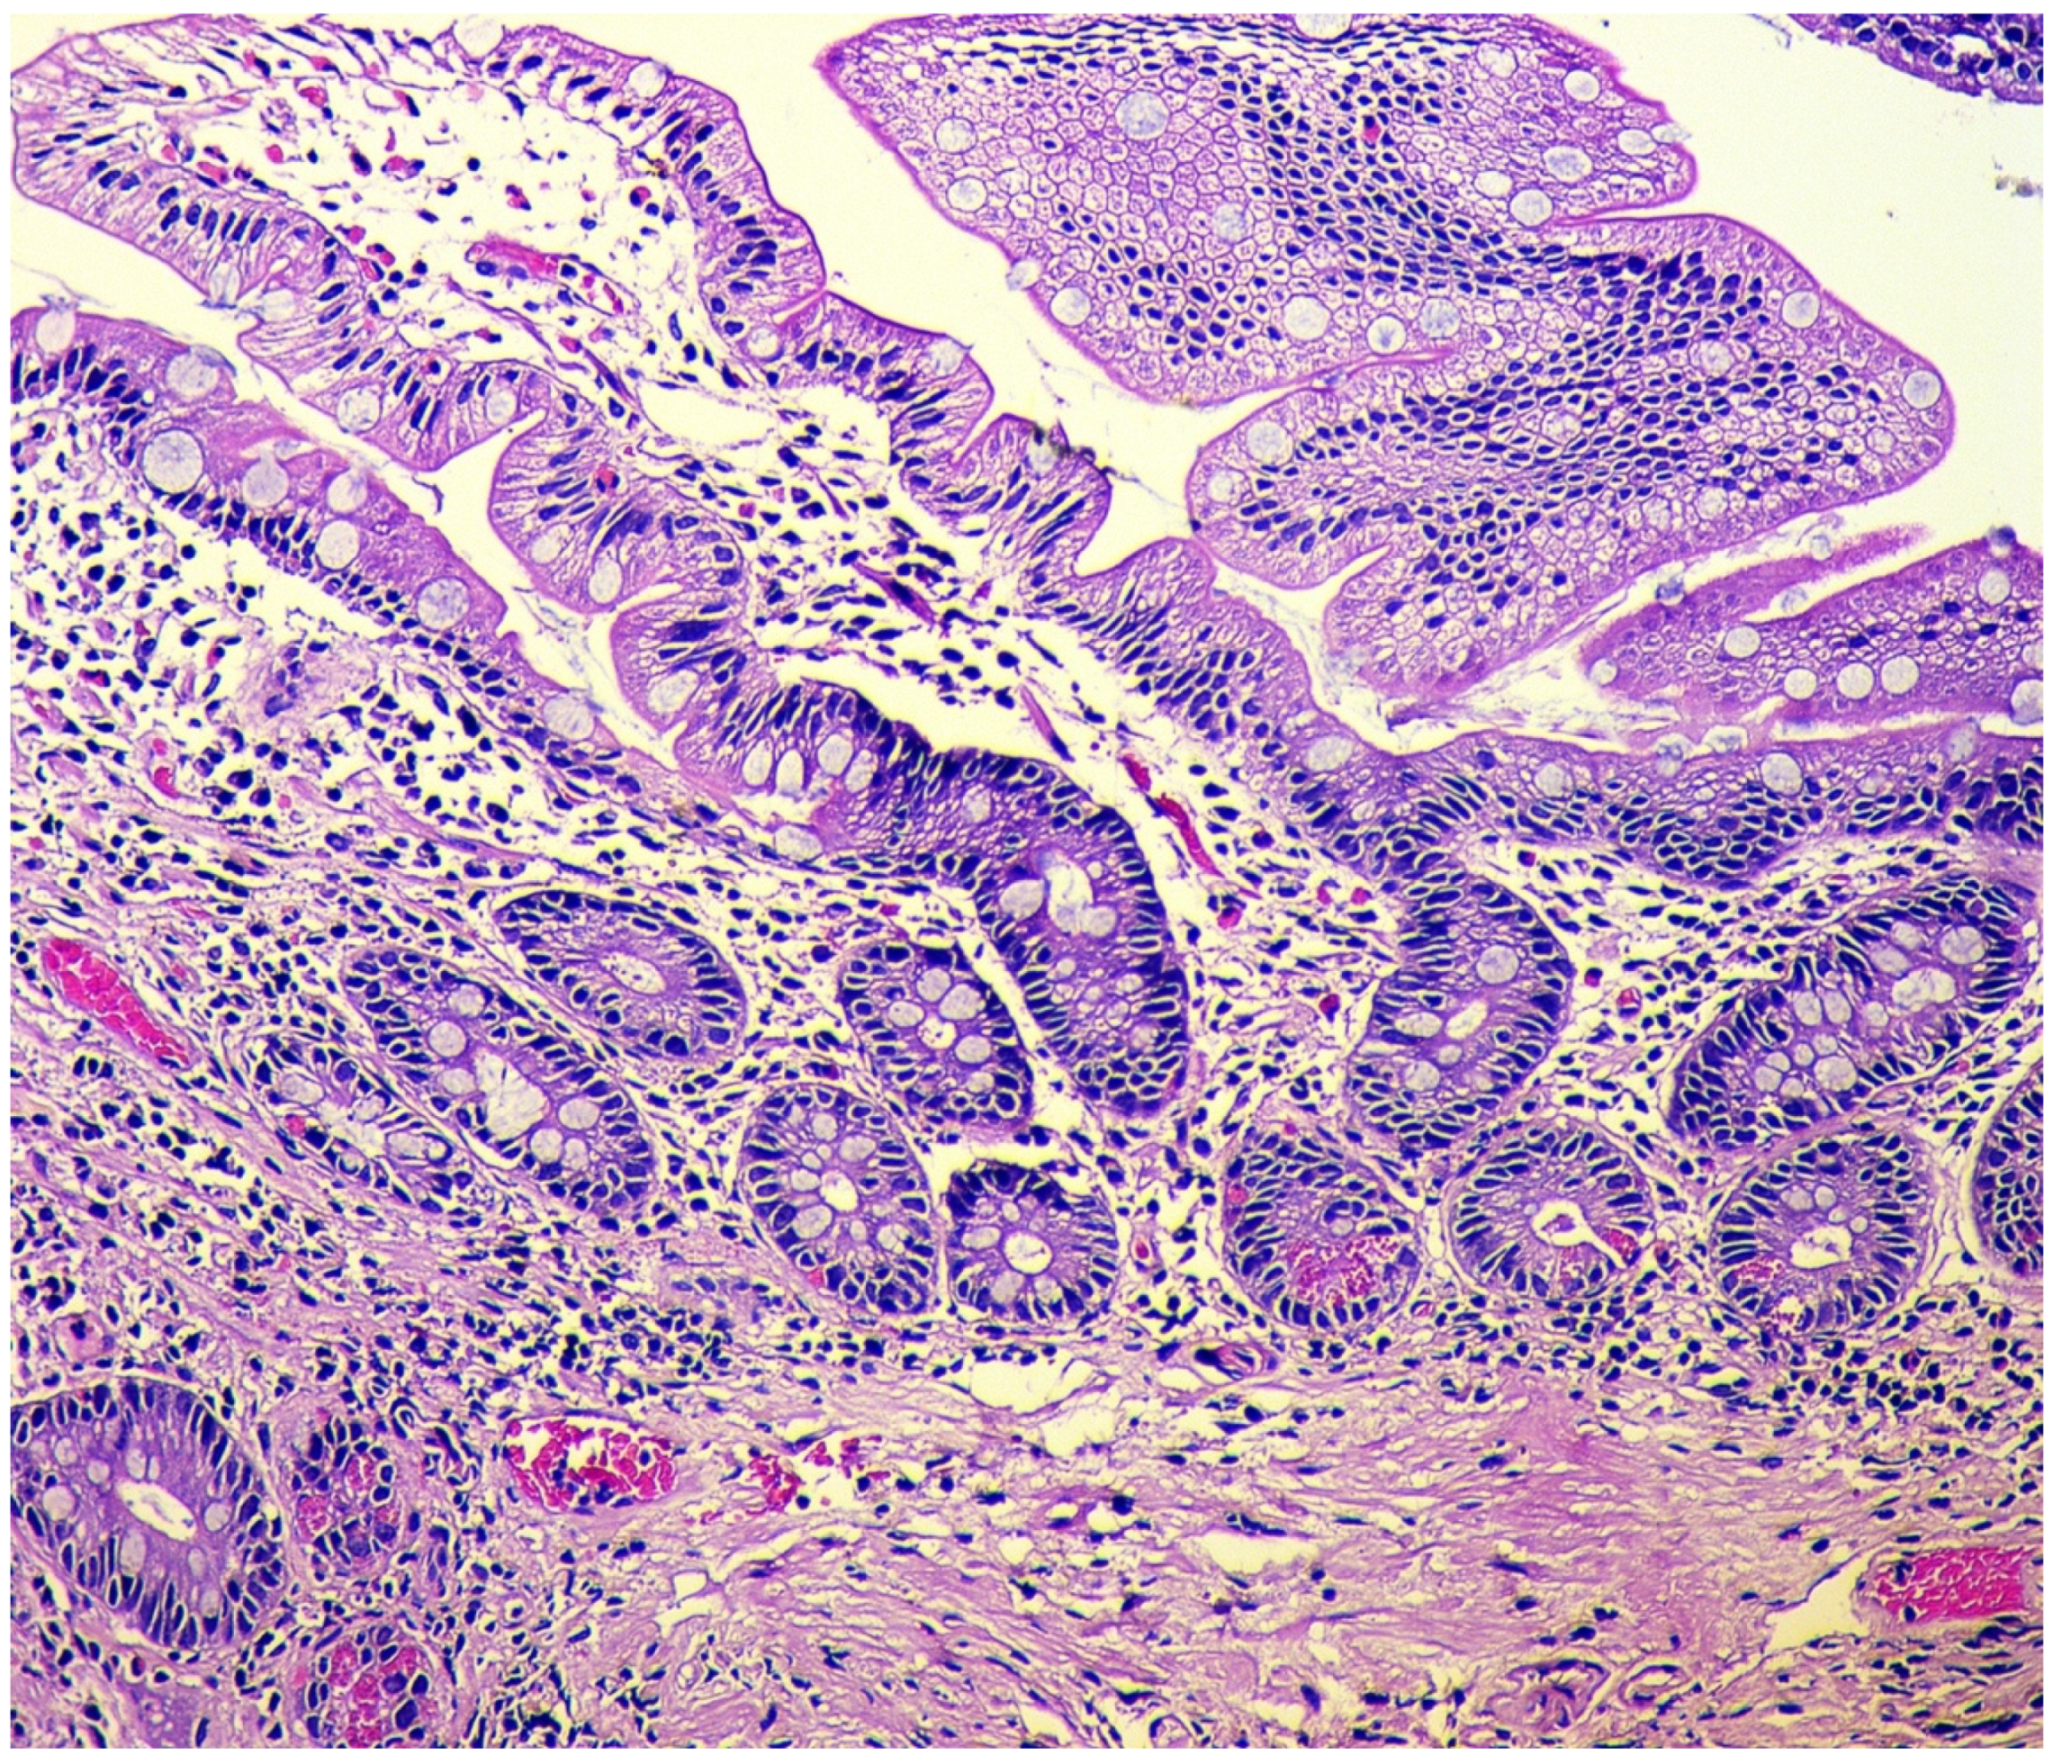

In the final stage of the disease, there is a pronounced reduction in acid-producing glands with the development of foveolar hyperplasia, the appearance of hypermucoidized cells, the formation of hyperplastic polyps, and an increase of the areas with pyloric (pseudopyloric), pancreatic, and intestinal metaplasia (Figure 3).

Figure 3.

Autoimmune gastritis. Biopsy from the gastric body. Severe intestinal metaplasia (type I, complete), with intestinalization of gastric mucosa and villous transformation with absorptive and goblet cells; Paneth cells with acidophilic granular cytoplasm are presented at the base of the glands. Hematoxylin and eosin stain. ×200 (from the personal archive of Professor S.I. Mozgovoi).

The classification of intestinal metaplasia is based on histochemical evaluation of mucins, as follows [47,48]: Complete intestinal metaplasia (type I): non-secretory absorptive cells with brush border and sialomucin-secreting goblet cells. Incomplete intestinal metaplasia type II with columnar cells secreting neutral and acid sialomucin, and goblet cells secreting mainly sialomucin but occasionally sulphomucin. Incomplete intestinal metaplasia type III with columnar cells secreting predominantly sulphomucin and goblet cells secreting sialomucin or sulphomucin.